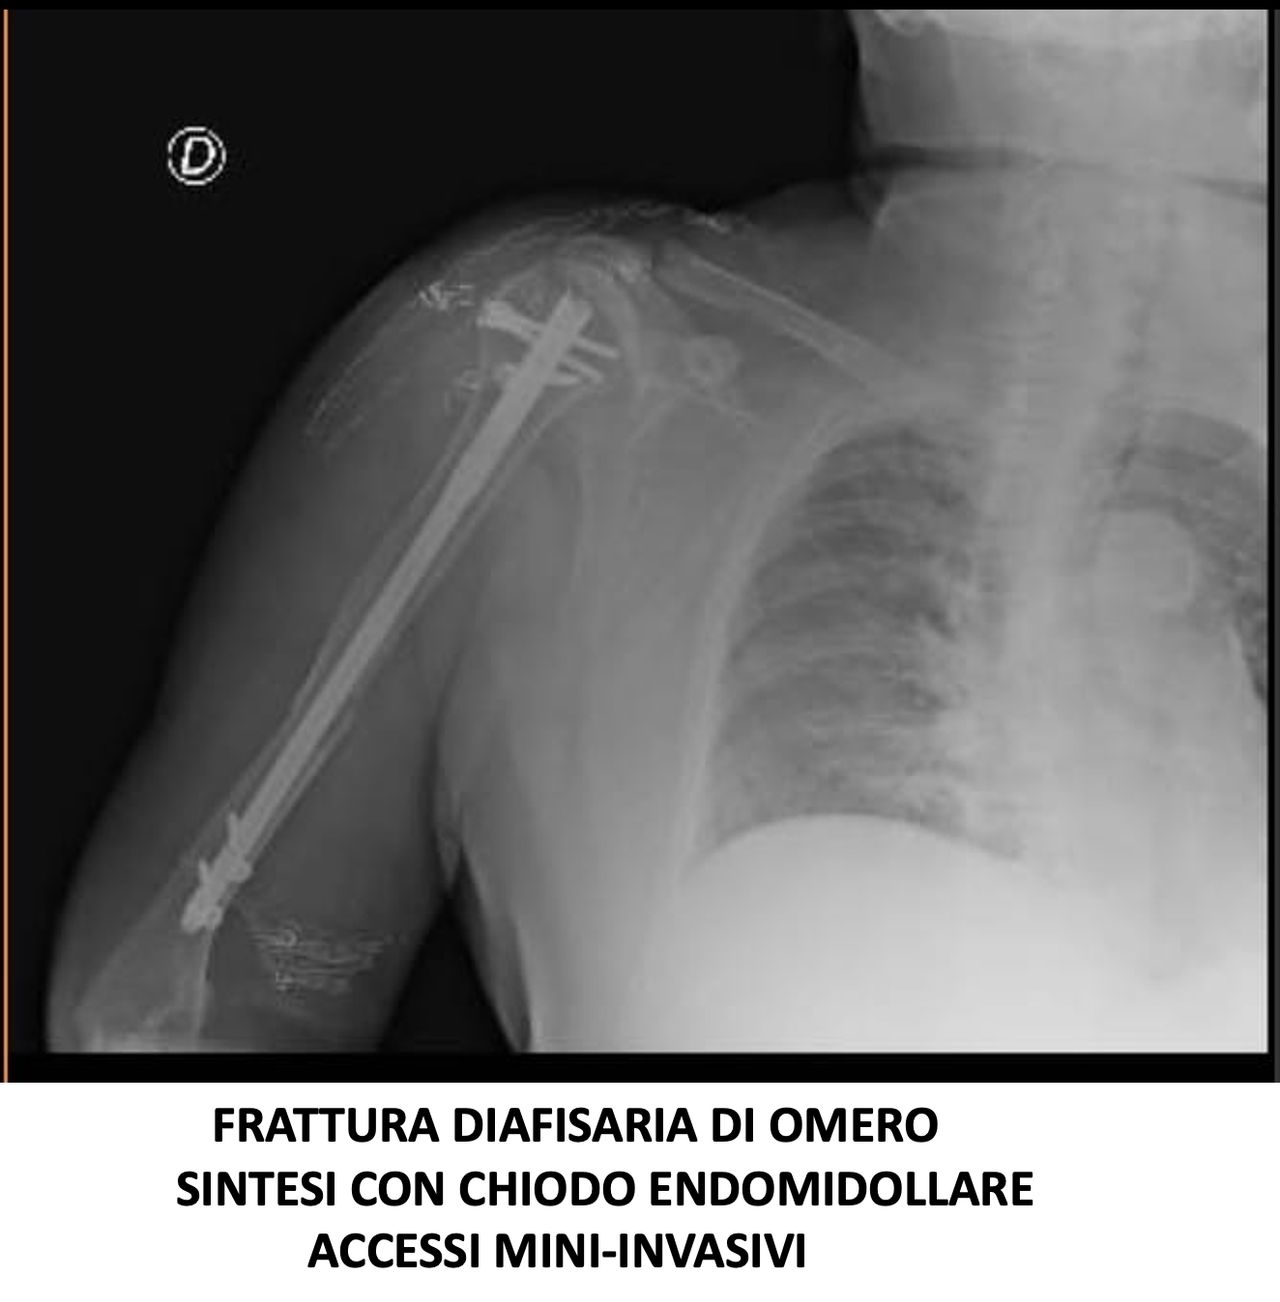

Svolge la sua attività presso l’Ospedale del Mare, occupandosi di chirurgia traumatologica, con predilezione alla protesica di ginocchio e medicina rigenerativa della cartilagine articolare.

• Ortopedia e traumatologia del sistema motorio